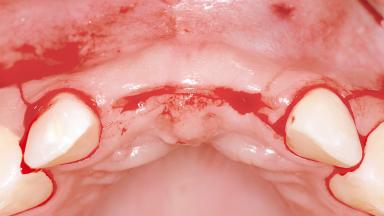

A 27-year-old female patient was referred to the Clinic of Oral Surgery and Stomatology of the University of Bern due to acute pain in the region of her two maxillary central incisors. The patient was in good general health. She reported a bicycle accident approximately 5 years earlier in which teeth 11 and 21 had been traumatized but neither fractured nor displaced. Several weeks after the accident, endodontic treatment was performed on both central incisors, although the patient did not recall the precise reasons for this decision. About 2 years ago, non-vital bleaching had been conducted, in accordance with the “walking-bleach” principle, due to progressive discoloration of teeth 11 and 21.